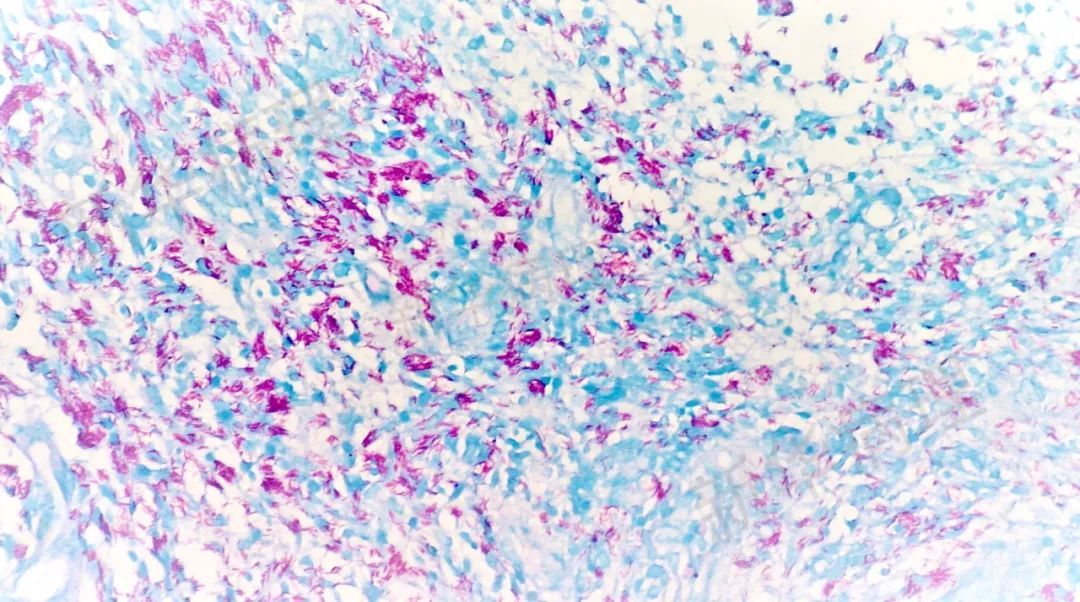

真菌(PASM染色)